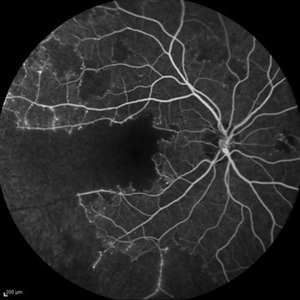

Behcet's Disease Behcet's DiseaseMar 13 2013 by Hamid Ahmadieh, MD Early phase FA of the left eye of a 23-year-old man with retinal vasculitis due to Behcet's disease . Photographer: Solmaz Shahmohammad, Negah Eye Center, Tehran Imaging device: Heidelberg Spectralis Condition/keywords: retinal vasculitis